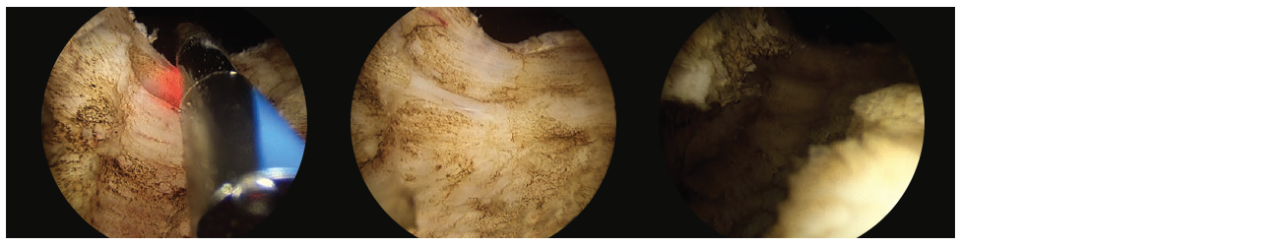

• Next, I vaporize a working space and demarcate the apex adjacent to the verumontanum. (Fig. 1)

2 scope images. Identifying anatomical landmarks (image shows left ureteral orifice). Figure 1: Demarcation of apical limits in front of veru.